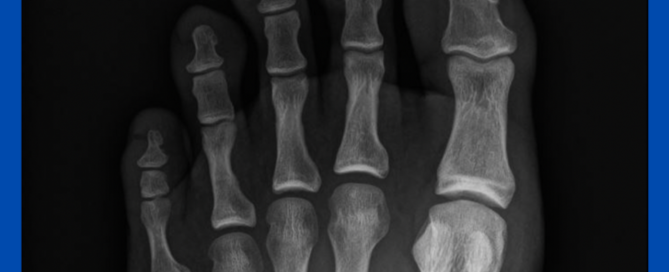

Subungual exostoses

Blog's main page This is one of a few subungual exostoses I see regularly throughout the year. Often when I see these cases, they have been treated as an ingrown [...]